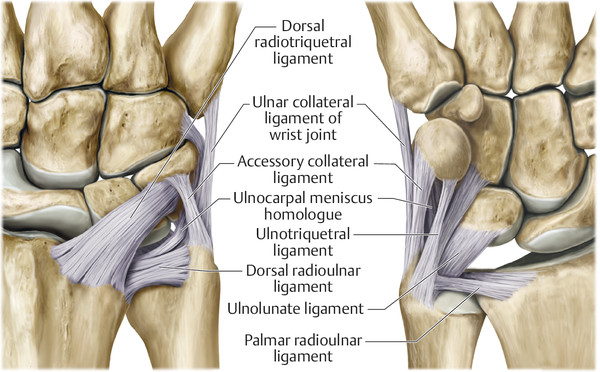

ligamentos

COMPLEJO FIBROCARTÍLAGO TRIANGULAR

ESTRUCTURA

FUNCIÓN

ESTABILIZA LA ARTICULACÓN RADIOCUBITAL DISTAL Y SEPARARÑA DEL CARPO Y DEL RADIO DISTAL.